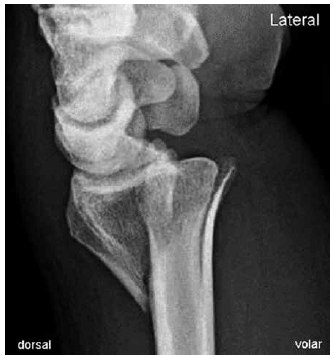

Analise a imagem a seguir e assinale a alternativa que apresenta a lesão observada e o mecanismo mais provável.